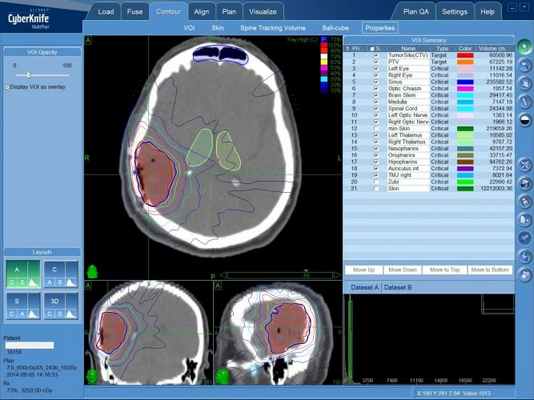

![Цифровой трехмерный план лечения глиобластомы на линейном ускорителе]()

Цифровой трехмерный план лечения глиобластомы на линейном ускорителе

В ряде случаев в лечении глиобластомы применяется радиохирургия на системе КиберНож. Этот метод лечения особенно эффективен в борьбе с опухолями головного мозга, поскольку проводится дистанционно, без хирургического вмешательства, разрезов и крови. Однако, радиохирургический метод показан при глиобластоме лишь в том случае, когда опухоль диагностирована на ранней стадии.

![План лечения глиобластомы на КиберНоже (радиохирургия)]()

План лечения глиобластомы на КиберНоже (радиохирургия). Внутри зоны, очерченной красным цветом будет сформирована высокая доза ионизирующего излучения, губительного для клеток опухоли

Наиболее эффективно является радиохирургия опухолей диаметром 2-4 см. Ограничений по форме самой опухоли, в сравнении с лечением на гамма-ноже, который способен довести равномерную дозу только в форме шара, КиберНож не имеет: любому пациенту четко указанная международными стандартами лечения высокая доза, которая призвана привести к разрушению опухолевых клеток, будет сконцентрирована во всем объеме глиобластомы, независимо от того, насколько сложной будет форма этой опухоли мозга.

Безопасность лечения глиобластомы обуславливается точным выявлением границ опухоли и взаимного расположения здоровых тканей головного мозга, проводимым определяется перед началом лечения методами КТ и МРТ с последующим построением пространственной 3D-модели, по которой мощный программный комплекс рассчитывает параметры подачи каждого из множества тонких пучков ионизирующего излучения, из которых и будет сформирована общая доза в опухоли.

Во время сеанса лечения система слежения КиберНожа сверяет с заранее сформированным планом лечения положение опухоли перед подачей каждого из пучков излучения, что сохраняет точность даже в случае движения пациента, минимизируя облучения здоровых тканей, окружающих опухоль головного мозга.